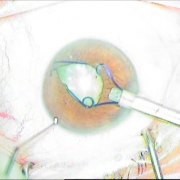

καταρράκτης με τραυματική

ρήξη οπ.περιφάκιου από

έγγχυση ANTIVGEF παράγοντα

του οπ. περιφάκιου